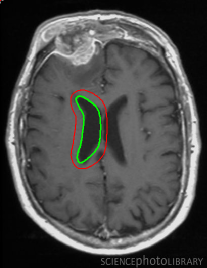

Figure 14: Segmentation of left lateral ventricle: (a) Initialization with a template (b) converged contour. Image source: Intermountain Medical Imaging, Idaho.

In Figure 13, we show the results for segmentation of endocardium in B-mode ultrasound images, an imaging modality where shape prior information is popularly[40, 41] used to counter the problem of broken/diffuse boundaries between the region of interest and its background. In Figure 14, we show an example where the template based formulation is able to overcome partial loss of signal due to occlusion and still segment the object reliably. We observe that, by incorporating prior knowledge of the shape, we can segment images with partial loss of structure and broken boundaries.